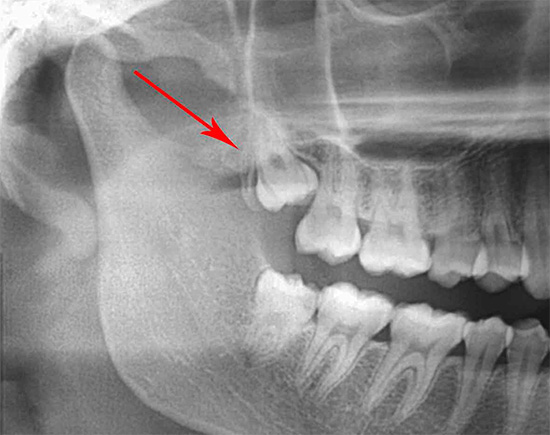

Devido ao fato de o dente do siso irromper por último, geralmente no final da arcada dentária, simplesmente não há espaço para isso. Com uma disposição estreita dos dentes e uma pequena mandíbula superior, o dente do siso (oitavo) pode não começar a entrar em erupção por um longo tempo, apoiando a parte da coroa na sétima adjacente. Nesse caso, surgem problemas sérios: dor, inchaço das gengivas e bochechas, e tudo isso leva ao fato de que é realizada uma remoção complexa do dente do siso na mandíbula superior, sobre a qual falaremos mais nuances mais interessantes e importantes em mais detalhes abaixo.

Antes de remover o 8o dente de cima (assim como o 6o, 7o, 5o e 4o), um raio-x é analisado para determinar os limites do seio maxilar em relação às raízes do dente: quanto mais próximo o local, maior o risco de perfuração ou perfuração.

- Perfuração do fundo do seio maxilar. Atualmente, devido à radiografia obrigatória antes da remoção do dente do siso essa complicação Não é tão comum, mas é um dos mais desagradáveis em todos os sentidos (veja a revisão abaixo). A prevenção é: controle de raios X antes da remoção, não o uso excessivo de força pelo médico em direção à raiz ou parte do dente removida, bem como um bom conhecimento da anatomia da mandíbula superior.